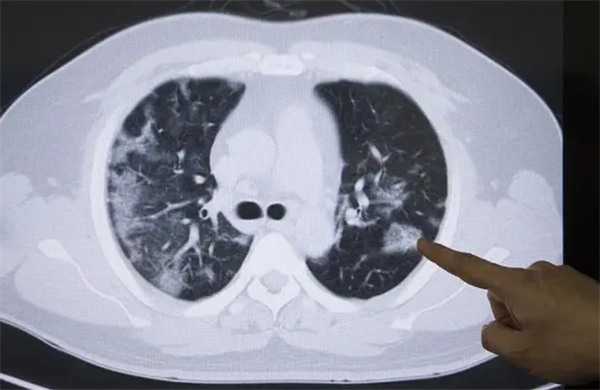

• 肺癌成为全球新增病例数最多癌症 早期有哪些症状?

虽然是生老病死,但我们也要做好预防疾病的发生,那么我们才能更健康的活着,然而说起癌症,相信很多人都是比较害怕的。根据世界卫生组织下属的国际癌症研究机构1日发布最新报告说,肺癌成为全球新增病例数最多癌症。 肺癌 2022年全球发病率最高的癌症又有哪些呢?据报告显示,发病率最高的癌症分别是肺癌、乳腺癌、结直肠癌。而我国肺癌发病人数和死亡人数已连续10年位居恶性肿…